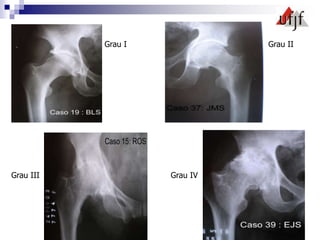

Classificação de Tönnis

 Grau Zero : Sem sinais de OA

 Grau 1: OA leve c/ aumento de esclerose ,

estreitamento articular mínimo, ausencia ou mínima

perda de esfericidade

 Grau 2: OA moderada c/ pequenos cistos,

moderado estreitamento articular , moderada perda

da esfericidade

 Grau 3: OA severa c/ grandes cistos , severo

estreitamento articular e severa deformidade da

cabeça

Grau I Grau II

Grau III Grau IV